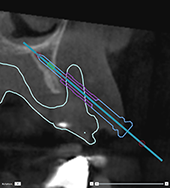

Correct inclination and depth of

anchor pins

To stabilize the surgical

template for implant insertion, anchor pins can be placed at strategic

positions. Their inclination

and depth are crucial.

The anchor pins can

also serve as lip retractors during surgery. Anchor pins spread too widely

within the arch could negatively affect mouth opening. A short-shaft version

of the anchor pin is available to mitigate this effect. Nevertheless,

the anchor pins should be planned so as to offer good access and should

not interfere with the implant sites.